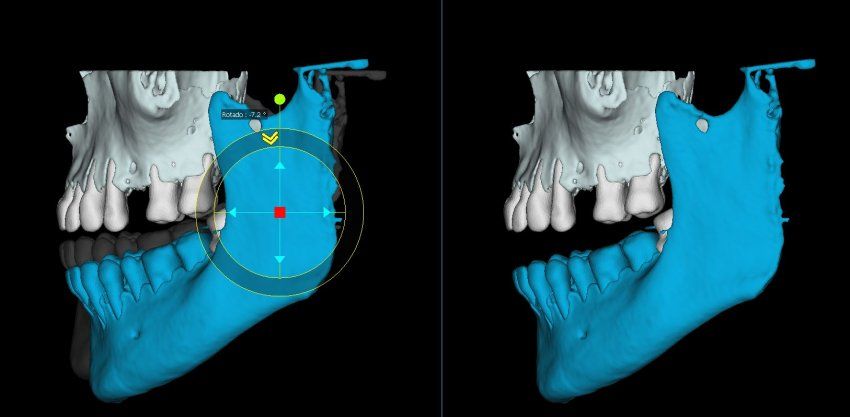

Green 16 es una avanzada proyección de imagen de rayos X digital 4-en-1, sistema que incorpora PANO, CEPH (opcional), CBCT y MODEL SCAN. Proporciona imágenes de alta calidad con menor radiación mediante la combinación de procesamiento de imágenes y acumuladas experiencias en imagen dental de VATECH. Esto mejorará su precisión de diagnóstico con un aumento de la planificación del tratamiento y la satisfacción del paciente.

Green 16/18 ofrece una gama de campos de visión seleccionables. Multi FOV permite al usuario seleccionar el modo FOV óptimo y minimizar la exposición a áreas que no son la región de interés. Seleccione el tamaño adecuado de FOV entre 16×9/18×10, 12×9/13×10, 8×9 y 5×5 basado en una particular necesidad de diagnóstico. Cubre la región del arco completo, seno y la ATM izquierda / derecha y es adecuado para la mayoría de los casos de cirugía oral así como la cirugía de implantes múltiples. También puede medir el volumen de la vía aérea.